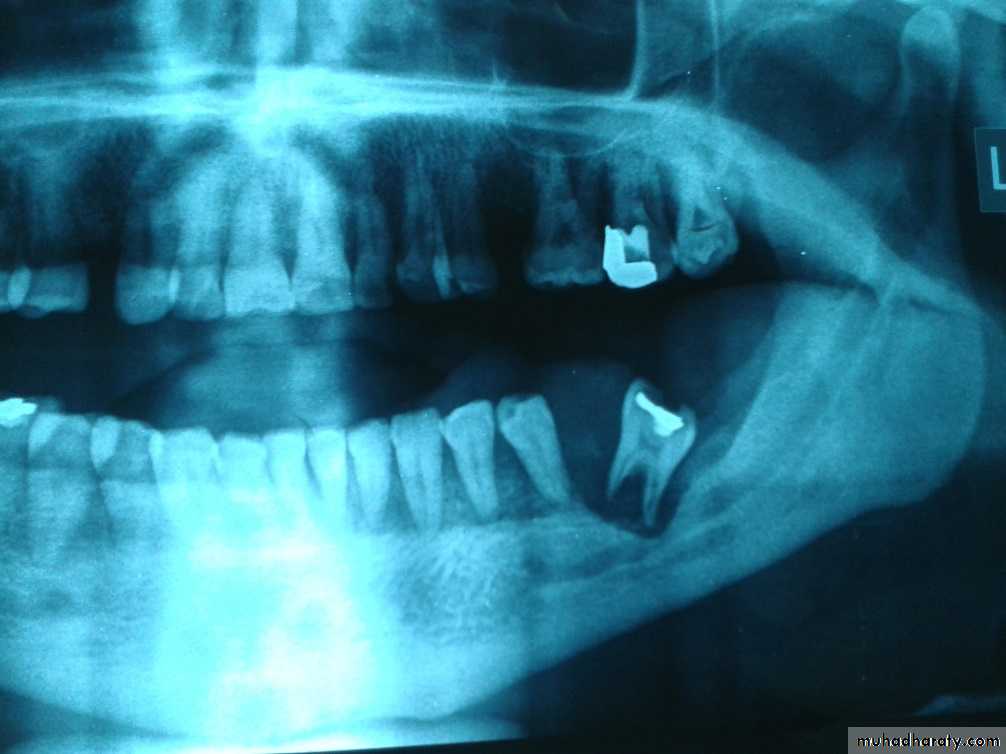

Raioraghical examination may demonstrate unlocular or multilocular types. Unilocular ameloblastomas may be confused with benign cysts. The tumors frequently absorbs the alveolus surrounding ,the roots of teeth and may absorb root ends.

Ameloblastoma grow by extension into adjacent tissues and may perforate the investing bone. A biopsy should precede treatment since

these tumors frequently present with individual characteristics.

Methods of treatment:

include extirpation, radical resection of the jaw. selective block excision and electro cauterization. Local excision of usually accessible tumor is indicated in the young.Provided, that they agree to regular follow - up and a radical resection when recurrence occurs. Recurrences are not unusual after curettage incomplete surgical treatment may stimulate tumor cell growth.